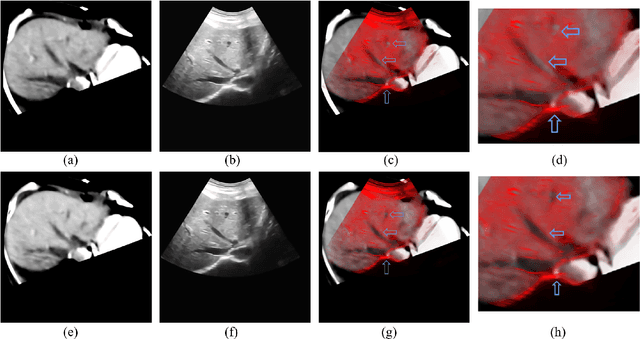

Abstract:The non-rigid registration between CT data and ultrasonic images of liver can facilitate the diagnosis and treatment, which has been widely studied in recent years. To improve the registration accuracy of the Demons model on the non-rigid registration between 3D CT liver data and 2D ultrasonic images, a novel boundary extraction and enhancement method based on radial directional local intuitionistic fuzzy entropy in the polar coordinates has been put forward, and a new registration workflow has been provided. Experiments show that our method can acquire high-accuracy registration results. Experiments also show that the accuracy of the results of our method is higher than that of the original Demons method and the Demons method using simulated ultrasonic image by Field II. The operation time of our registration workflow is about 30 seconds, and it can be used in the surgery.